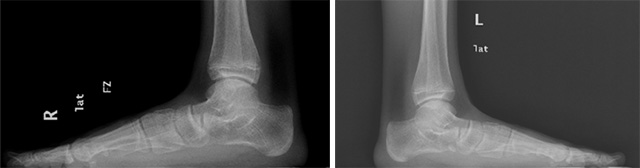

圖為患者扁平足負(fù)重位影像學(xué)資料

患者入院后,科室針對患者病情及時(shí)召開病歷討論專題會(huì),經(jīng)分析:患者相關(guān)查體及檢查后考慮患者為:1.雙側(cè)僵硬性扁平足;2、右足副舟骨;3、右側(cè)腓骨長肌腱脫位。患者左足癥狀輕,考慮繼續(xù)保守治療,右足癥狀明顯,考慮手術(shù)治療。